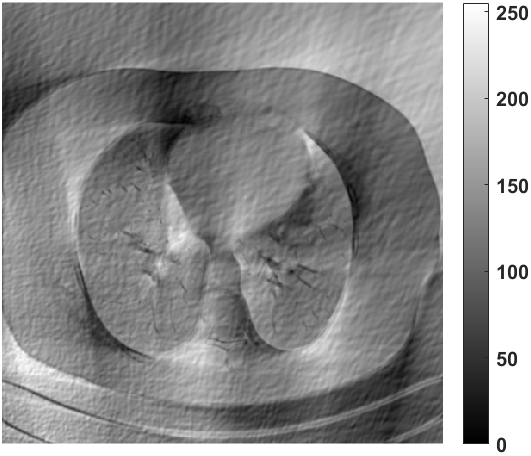

Next, we numerically compare the condition numbers of the system matrices for both the low-resolution and original reconstruction problems by 1-norm, 2-norm and -norm, respectively. As shown in Fig. 8, we can observe that the condition numbers of the low-resolution reconstruction problem are much smaller than the original reconstruction problems for different scanning angles, which are consistent with our theoretical analysis. In fact, larger condition numbers allow for undesired solutions, which also numerically satisfy the forward model (1). More importantly, the constraint in our model (2) can help to find better solution from the null space, which has already been perfectly demonstrated by our numerical experiments.

What is more, as shown in Table III, IV and V, the smaller the down-sampling rate, the better the reconstruction result. Since the quality of the image prior decreases as the resolution decreases for the limited-angle reconstruction problems, there is a trade-off between the resolution and the quality. Thus, we track the relationship between the resolution of the low-resolution image priors and the performance of our LRIP-net. As shown in Fig. 9, the best reconstruction results are obtained using the low-resolution image prior with down-sampling rate . Although the smaller the condition number of the system matrix, the better the numerical stability of the solution, it does not mean that the better the performance of our LRIP-net.